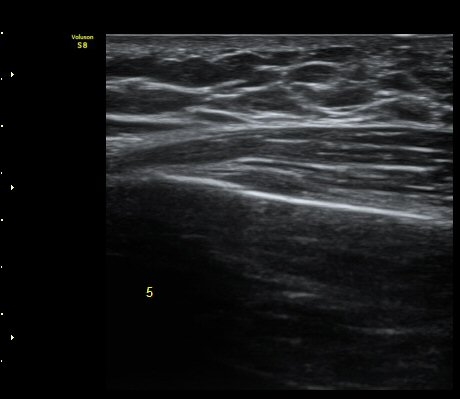

ÃÊÀ½ÆÄ °Ë»ç

¹Ì¼¼ÇÏ°Ô °¥ºñ»À ÇÇÁú°ñ ¿¬°á¼º ¼Ò½Ç°ú ¿¬ºÎÁ¶Á÷ ºÎÁ¾ÀÌ °üÂûµÊ(loss of cortical continuity and soft tissue swellingof rib)   »çÁø 1, 2, 3

3, 4,, 5 ¹øÂ° °¥ºñ»À °ñÀýÀÌ È®ÀεÊ.